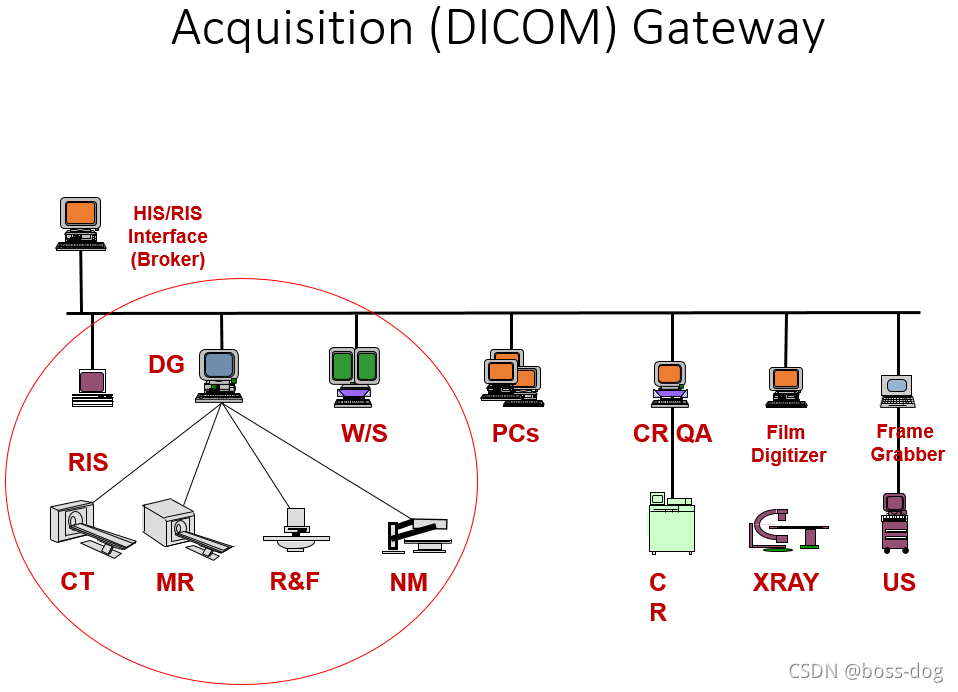

Acquisition Gateways(采集网关)

Acquisition gateway的作用:

1.需要把图片进行一定的压缩或者解压,同时要保证图像的安全和完整性

2.转换为PACS格式(header, byte-order, matrix size)

3.如果图片到的很多的话,需要根据优先级进行一定的调整

4.为多个采集网关共享工作负载和无故障点